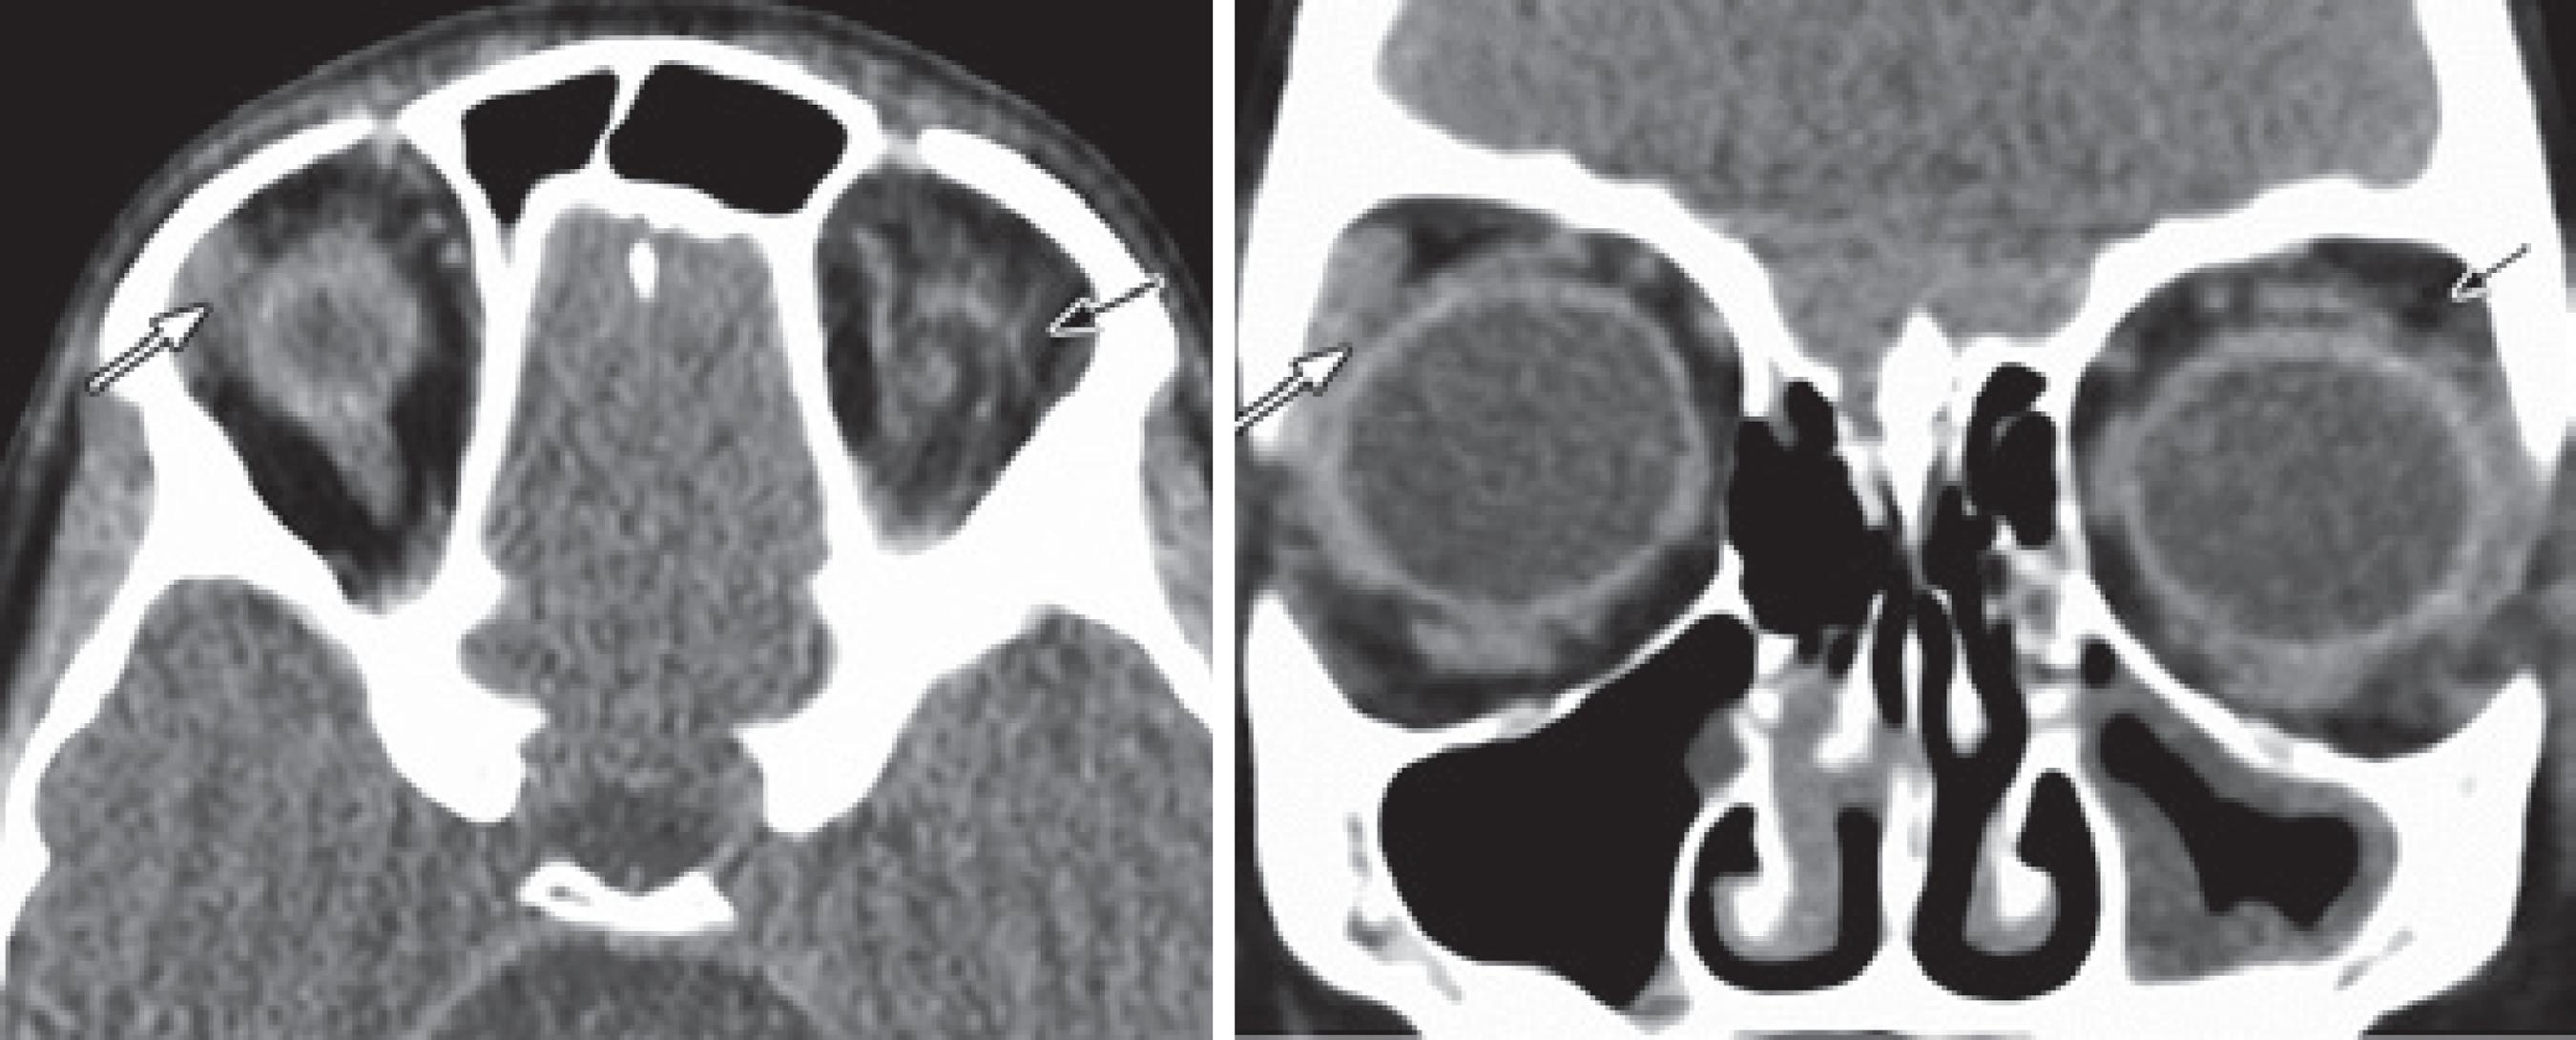

A seven years and eight month old male with congenital upper lid ptosis of the left eye had undergone levator resection two years before revision of overcorrection and lower punctal occlusion. On examination his visual acuity was 20/20 in the right eye and 20/40 in the left eye. MRD1 was 4 mm the right eye and 1 mm in left eye. LPS function was 6 mm in the left eye. Biomicroscopy showed diffuse punctate keratopathy in the left eye despite a long-term non-resorbable plug (SmartPlug; Medennium Inc., Irvine, CA, USA) inserted on the lower lacrimal punctum. Computed tomography imaging indicated the absence of the left lacrimal gland (Figure 2). The parents were not satisfied with the cosmetic appearance of the child and requested revision of the ptosis surgery. During this third procedure, absence of the orbital lobe of the lacrimal gland was noted in association with scar tissue in the lacrimal fossa. The remnants of the levator were identified and re-advanced successfully. Dry eye was treated with frequent instillation of artificial tears and insertion of a punctal plug in the upper lid.